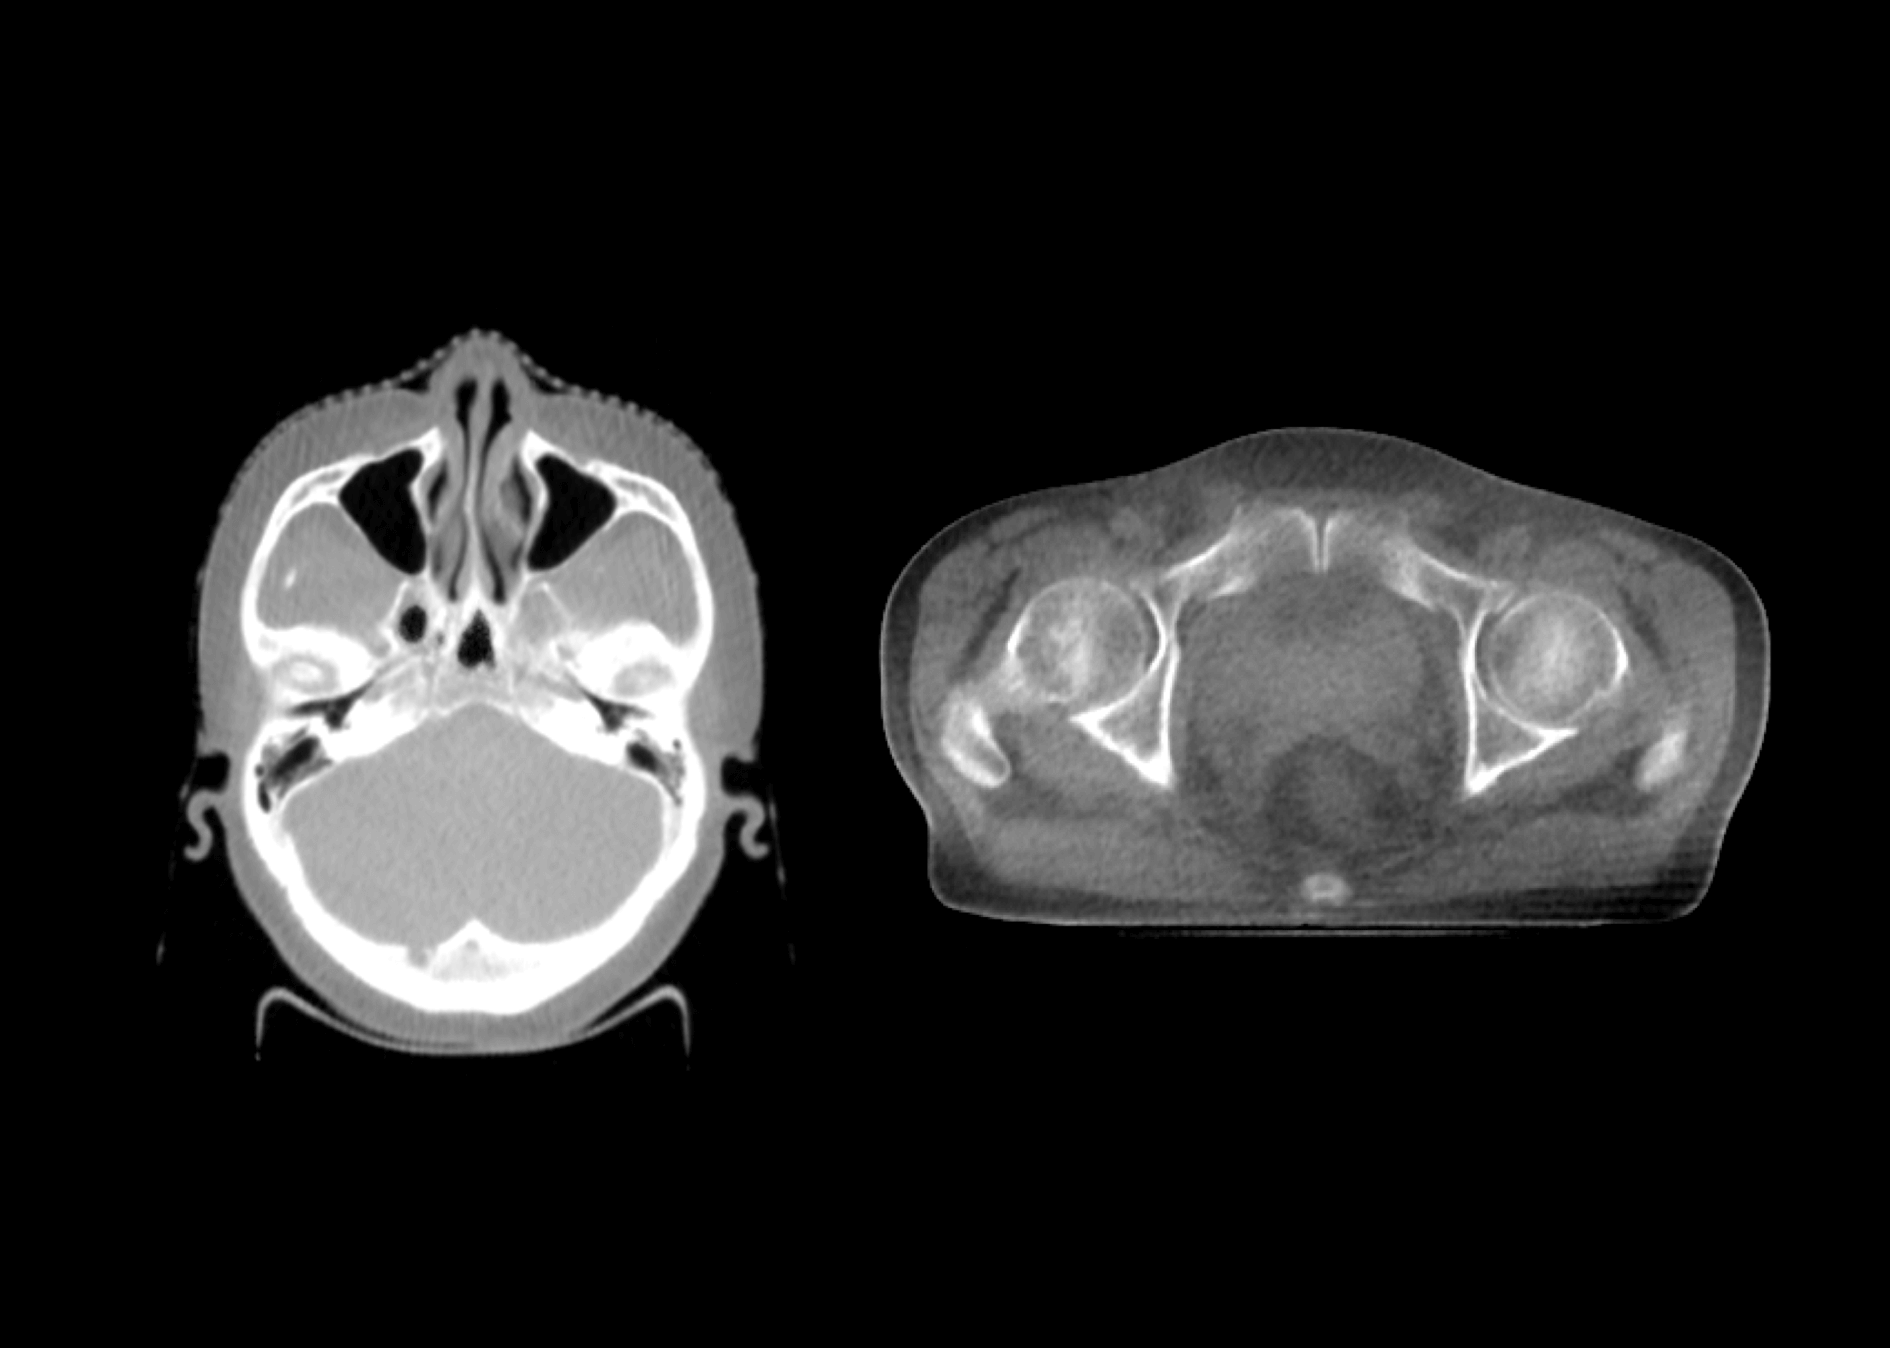

成就类kV级CBCT成像

深度调能成像技术

1.5MeV电子束打靶,使得千伏级成像光子占比更大,图像质量媲美常规kV级CBCT。

影像引导成像束流与治疗束流同一等中心,带来更高的图像引导精度。

一键CBCT成像,自动配准,自动移床,自动避撞,高度自动化,有效提升效率。